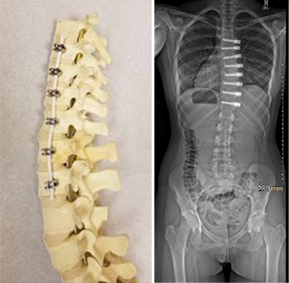

(Left) VTB hardware and postop X-ray

(Right) Fusion hardware and postop X-ray